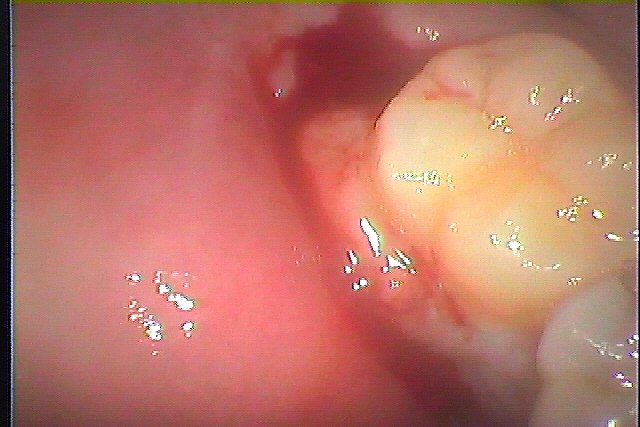

当医院へ来院時にはかなり腫れていました

沢山膿が出てきていました